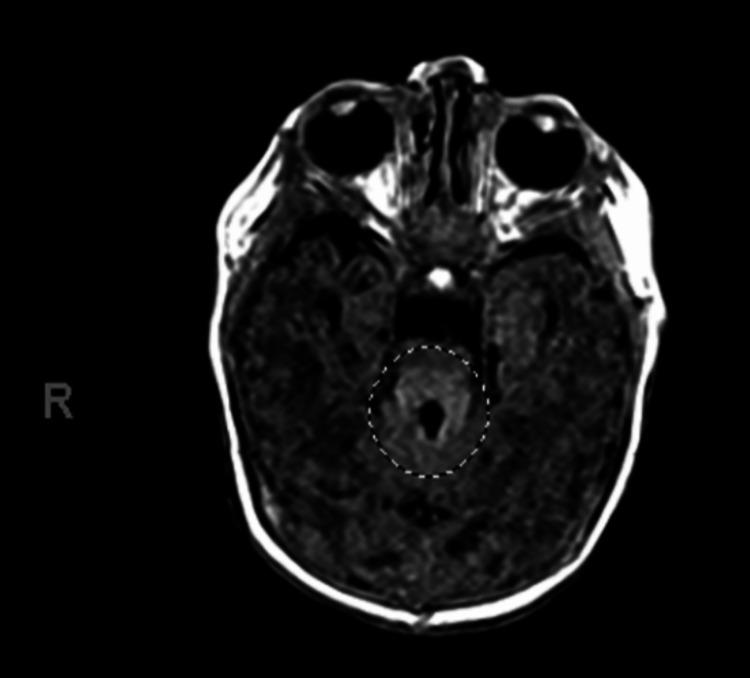

Joubert syndrome is an uncommon, autosomal recessive disorder characterized by abnormal brain development involving the underdevelopment or absence of the cerebellar vermis. The classic clinical features include developmental delays, hypotonia, abnormal eye movements, and hyperpnea. On brain magnetic resonance imaging (MRI), an essential finding for the diagnosis of Joubert syndrome is a cerebellar and brainstem malformation called the molar tooth sign, characterized by a hypoplastic cerebellar vermis with dysplasia of the superior cerebellar peduncles. Here, we describe a case of a two-month-old female with an atypical presentation of Joubert syndrome. Her initial clinical presentation included respiratory distress and concerns for reflux complicated with aspiration pneumonia. Early recognition of clinical and radiologic findings for Joubert syndrome enables an early diagnosis, and therefore timely interventions for improving the child's development and quality of life.

乔伯特综合征是一种罕见的常染色体隐性疾病,其特征是大脑发育异常,包括小脑蚓部发育不全或缺失。典型的临床特征包括发育迟缓、肌张力减退、异常眼动和呼吸急促。在脑部磁共振成像(MRI)上,诊断乔伯特综合征的一个关键发现是一种称为磨牙征的小脑和脑干畸形,其特征是小脑蚓部发育不全,伴有小脑上脚发育异常。在此,我们描述了一例两个月大女性乔伯特综合征的非典型表现。她最初的临床表现包括呼吸窘迫以及对反流并伴有吸入性肺炎的担忧。早期识别乔伯特综合征的临床和影像学表现有助于早期诊断,从而能够及时进行干预以改善患儿的发育和生活质量。